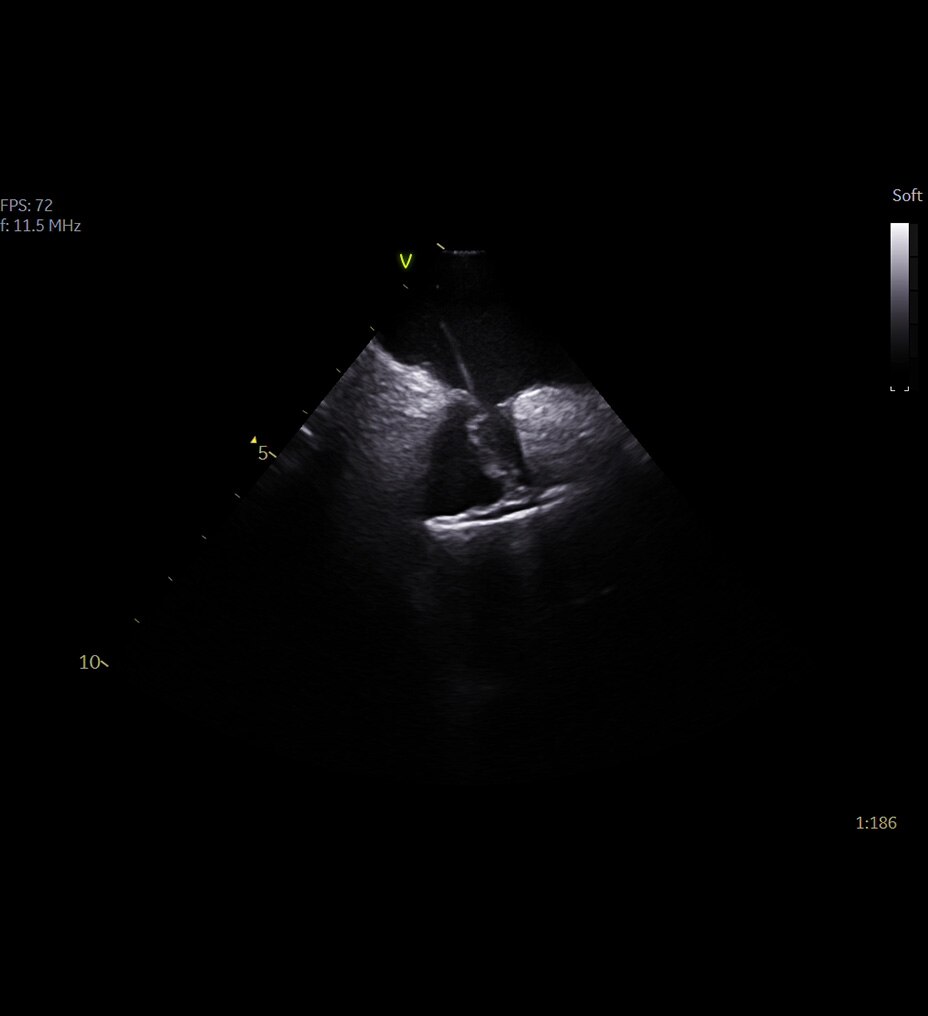

Üstün görüntü kalitesi

Daha net görüntüler daha kolay tanılar anlamına gelir ve derin öğrenme teknolojimiz AIR™ Recon DL ile olağanüstü kalitede görüntüleri daha hızlı elde edebilirsiniz. Çok çeşitli anatomiler için en net sonuçları sağlayarak MR görüntülerini görüntüleme biçiminizde devrim yaratır.

Ayrıca, göz yorgunluğunu azaltabilen okunması kolay, yüksek kaliteli taramalarla elde ettiğiniz görüntülerin kalitesinden daha emin olarak oluşturulan raporların daha iyi bir genel deneyime sahip olmasını sağlayabilirsiniz.